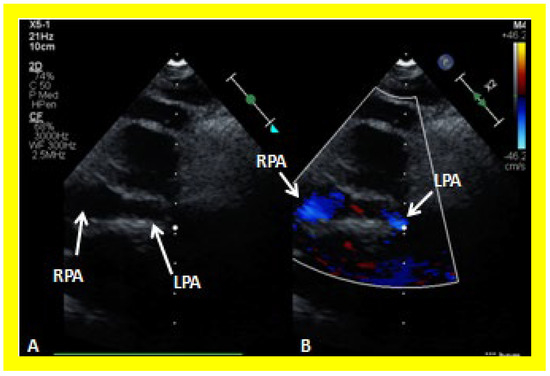

The relationship of the great arteries is examined next in order to classify them into various types, as mentioned above. The relationship of the great arteries (Figure 2, top) is established by following the vessels arising from the ventricles until the pulmonary artery (PA) bifurcation or aortic arch. In Type I patients with normally related great arteries, the aorta arises from the LV (Figure 10) and in Type II patients with transposition of the great arteries, the PA arises from the LV (Figure 11; Figure 12). In Type II patients, the blood vessel arising from the LV should be traced to demonstrate its branching into the right and left PAs (Figure 11; Figure 12). In Type III patients, it may be a little more difficult to assign the great artery relationship and, sometimes, other imaging studies, including angiography, may be needed to define the great artery relationship. In Type IV with truncus arteriosus, the limited data suggest that this can be performed by echocardiography (Figure 13; Figure 15). In the example shown [31], the atretic tricuspid valve (Figure 13a and Figure 14a), VSD (Figure 13b and Figure 14b), hypoplastic RV (Figure 14a), single vessel (truncus) arising from the heart (Figure 13c,d, and Figure 14c,d), and origin of the PA and its division into branch PAs (Figure 13d, and Figure 14c,d) were demonstrated.

In Type II patients, the VSD may be small, causing obstruction to blood flow to the systemic circuit, and, therefore, the size of the VSD should be ascertained by 2D (Figure 11 and Figure 12), color Doppler (Figure 12), pulsed (Figure 15) and CW Doppler, as necessary. In these Type II patients, a high VSD velocity is indicative of subaortic obstruction. Interrogation of the LV outflow and PA region may reveal pulmonary or subpulmonary stenosis; the higher the velocity, the more severe is the obstruction. Studies from the suprasternal notch may show aortic coarctation (Figure 16), which is common in patients with Type II anatomy.

Figure 12. A selected video frame from a parasternal long axis view with color flow mapping of another patient with tricuspid atresia and transposition of the great arteries demonstrating the left atrium (LA), left ventricle (LV), a small right ventricle (RV) and a moderate sized ventricular septal defect (VSD). The vessel coming off the LV bifurcates into right (RPA) and left (LPA) pulmonary arteries. Reproduced from Reference [29]. PA, pulmonary artery.

Applsci 11 09472 g012